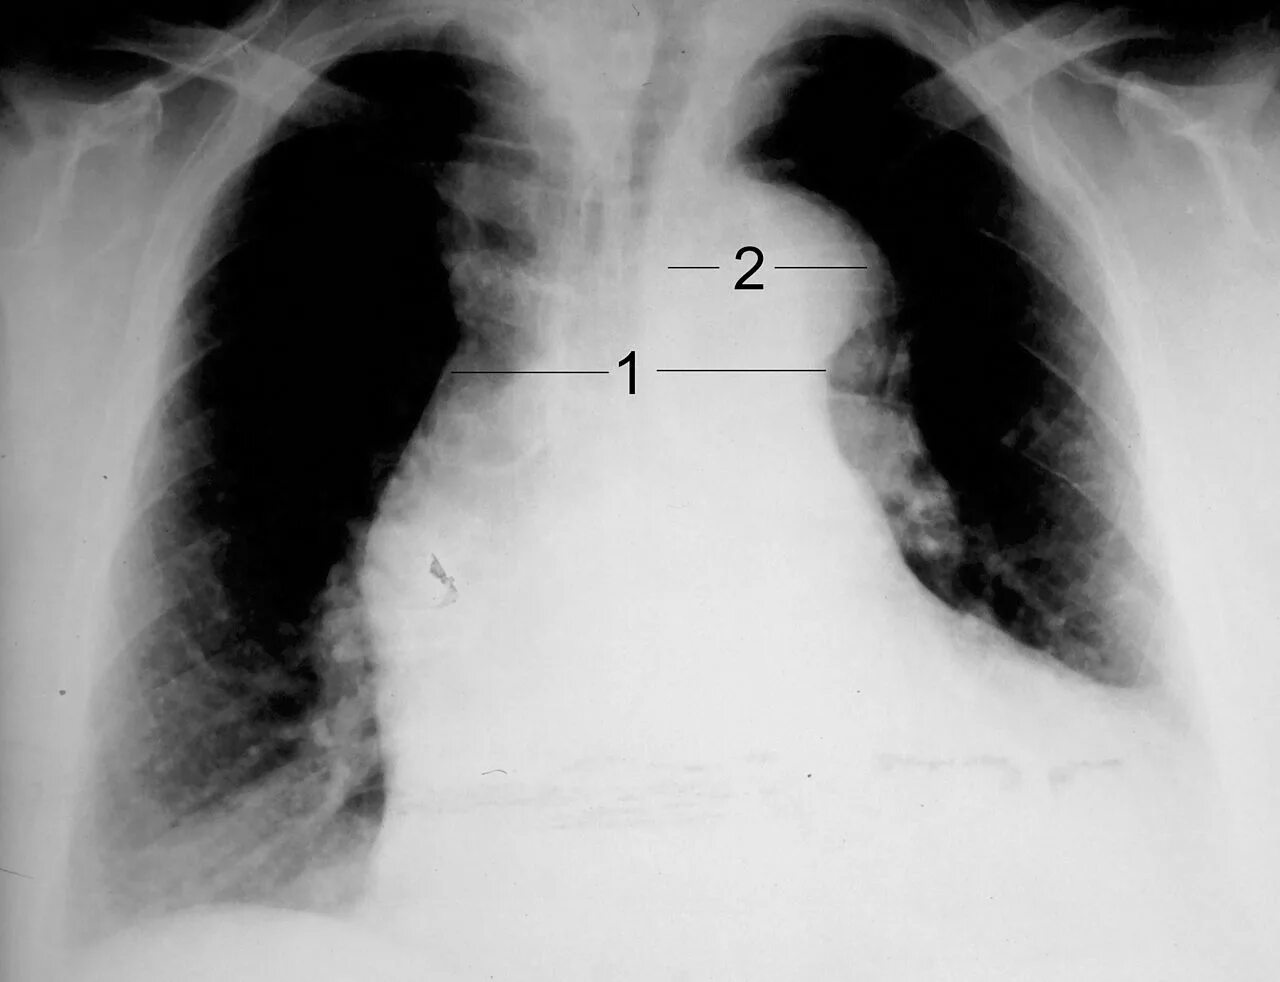

Что значит аорта уплотнена на флюорографии